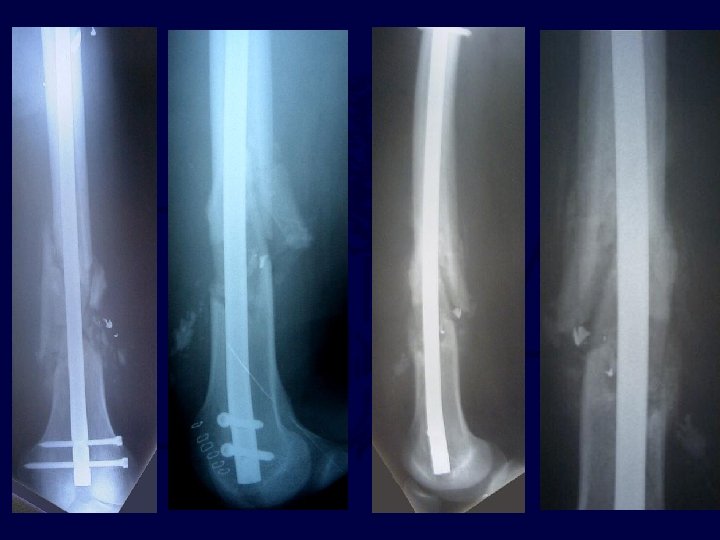

• • • 19 y. o. male GSW to leg ABI =. 95 Neuro intacy Radiographs – Comminuted fracture femoral shaft

• 2 months post op • Early healing with callus forming • Weight Bearing as tolerated, No pain